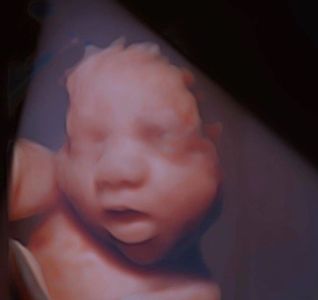

With our advanced 3D/4D/HD Live ultrasound technology, you can watch those tiny fingers flex and

see the sleepy smiles form on your baby's face. You and your loved ones can marvel in the

miracle of pregnancy together in our Baby-Viewing Theater, a comfy atmosphere with a

100-inch screen for a squint-free experience.